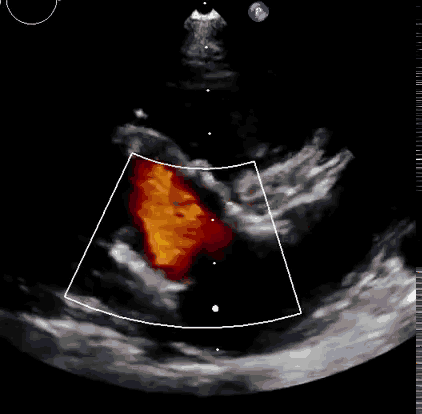

本次臨床前研究經(jīng)右側頸靜脈置入LuX-Valve Plus輸送系統(tǒng)可調彎鞘管,在DSA及超聲引導下將人工三尖瓣瓣膜植入到原有三尖瓣位置,利用獨特的錨定技術將人工瓣膜支架可靠固定在預定的位置。

上海中山醫(yī)院葛均波院士、錢菊英院長、周達新教授、潘文志教授、潘翠珍教授、李偉教授共同完成此次臨床前研究。術后葛均波院士對Lux-Valve Plus的器械操作性能給予了高度評價,DSA和超聲影像也顯示出在本次研究中Lux-Valve Plus的安全性和有效性俱佳。